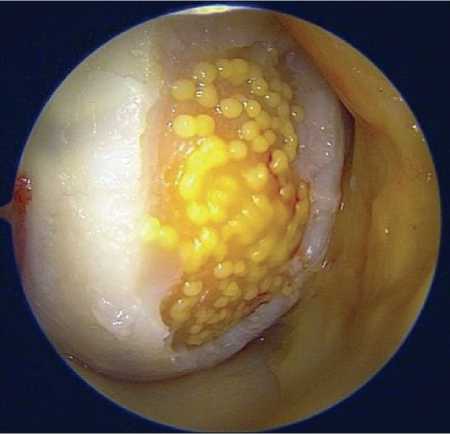

На первом этапе пациентка была госпитализирована в отделение травматологии и ортопедии УКБ №1 Сеченовского университета для проведения диагностической артроскопии левого коленного сустава с забором костно-хрящевых фрагментов. При артроскопическом исследовании выявлен хрящевой дефект медиальной фасетки надколенника размерами 15 × 41 мм (6,15 см²) с неровными краями; других дефектов хряща и структурных повреждений коленного сустава не обнаружено (Рисунок 4). Для последующего клеточного культивирования выполнен забор биоматериала – трёх костно-хрящевых цилиндров диаметром 6 мм. Проведён обильный лаваж сустава, после чего произведено послойное ушивание операционной раны и наложение асептической повязки. Пациентка была выписана на следующий день после контрольной перевязки с рекомендациями, соответствующими стандартному послеоперационному ведению после артроскопических вмешательств.

Рисунок 4. Повреждение хряща левого надколенника на первой артроскопии коленного сустава

Рисунок 5 . Имплантация хондросфер на поверхность дефекта хряща надколенника